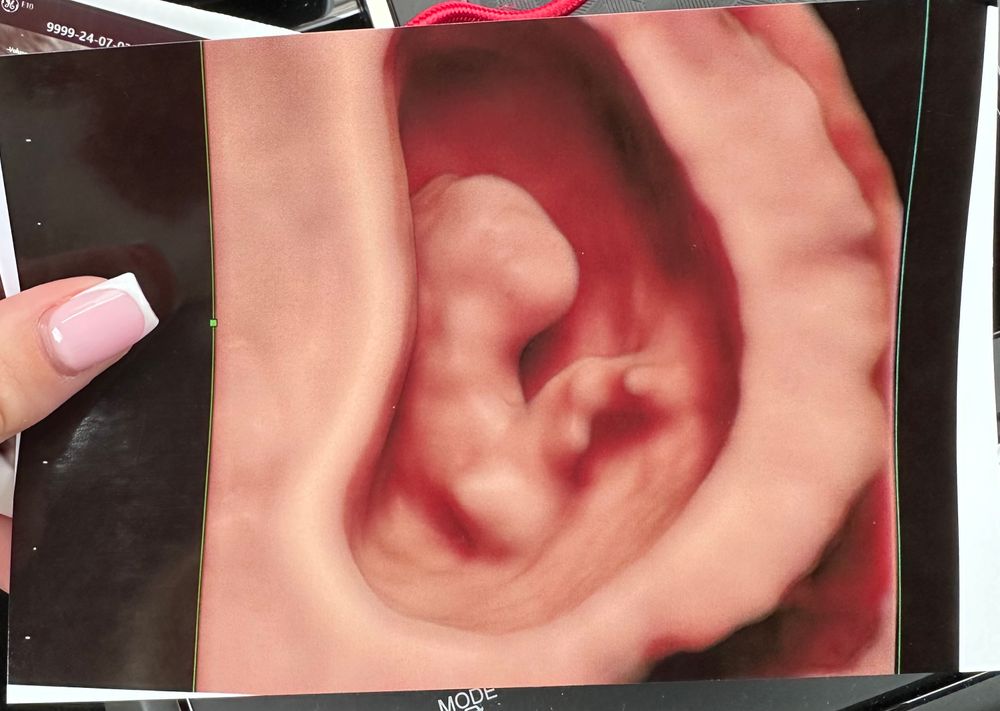

P.s. Нам сделали фото нашей ляльки 2Д и 4Д😍😍😍😍

Сегодня нам 9 недель и я решила сходить на УЗИ к самому лучшему доктору УЗИ в нашем городе😍 Она невероятная, от нее веет теплом, добротой и спокойствием, максимальной энергией, любовью к своему делу и своим пациентам, профессионализм зашкаливает, чтобы попасть к ней люди записываются за месяц, следят за ее инстаграмом, чтобы не пропустить запись, первый скрининг решила делать именно у нее однозначно! У нее самая новейшая аппаратура, она всем малышам устраивает фотосессии, она ВОЛШЕБНАЯ!💕Сказала, что все у нас замечательно, гематома исчезла, срокам мы соответствуем, все хорошо!